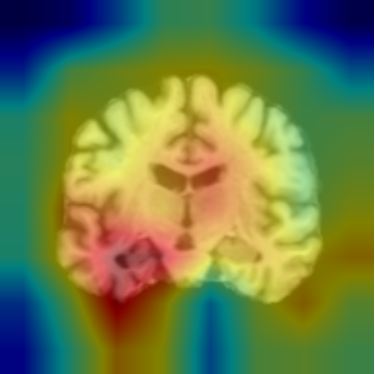

- 특히, 저희 들이 다룬 것은 누군가의 뇌 이미지를 사용해 치매 정도, 치매 예측을 하는 것이기에 우리들이 의료 종사자한테 어느 선에 맞춰야 하는지 많은 혼란이 있었습니다.

- 그렇게 XAI를 이용해 각 모델이 의료 종사자가 쉽게 사용할 수 있는 진단 대시보드를 만드는 것으로 결정했습니다.